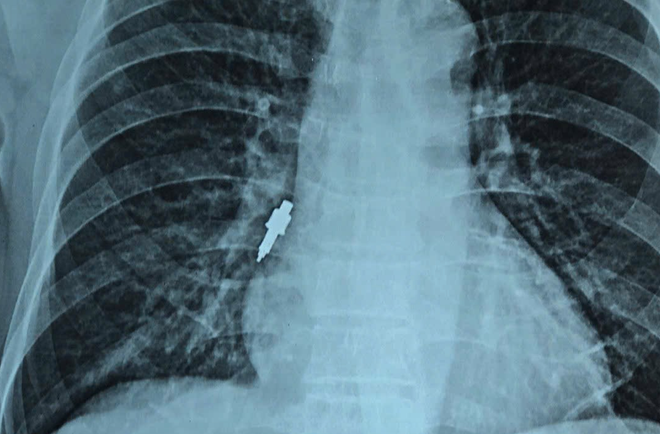

در تاریخ ۲۶ نوامبر، بیمارستان فرندشیپ اطلاع داد که پزشکان بخش تنفسی بیمارستان، مورد نادری از جسم خارجی برونش، یک ابزار دندانپزشکی فلزی به طول ۲.۵ سانتیمتر، را که هنگام انجام ایمپلنتهای دندانی در یک کلینیک خصوصی به داخل مجاری تنفسی افتاده بود، دریافت و با موفقیت درمان کردهاند.

سپس بیمار دچار سرفه خفیف و مداوم شد. در ۲۵ نوامبر، سرفهها بدتر شد و خانوادهاش او را برای عکسبرداری به بیمارستان بردند که در نتیجه یک جسم خارجی در برونش راست او کشف شد، بنابراین بلافاصله او را به بیمارستان دوستی منتقل کردند.

در بیمارستان، برای بیمار برونکوسکوپی اورژانسی جهت خارج کردن جسم خارجی تجویز شد. با این حال، فرآیند خارج کردن جسم خارجی با چالشهای زیادی روبرو بود زیرا جسم خارجی صاف، ساخته شده از فولاد ضد زنگ و بزرگ بود؛ بزرگترین قطر آن تا ۱ سانتیمتر و طول آن ۲.۵ سانتیمتر بود.